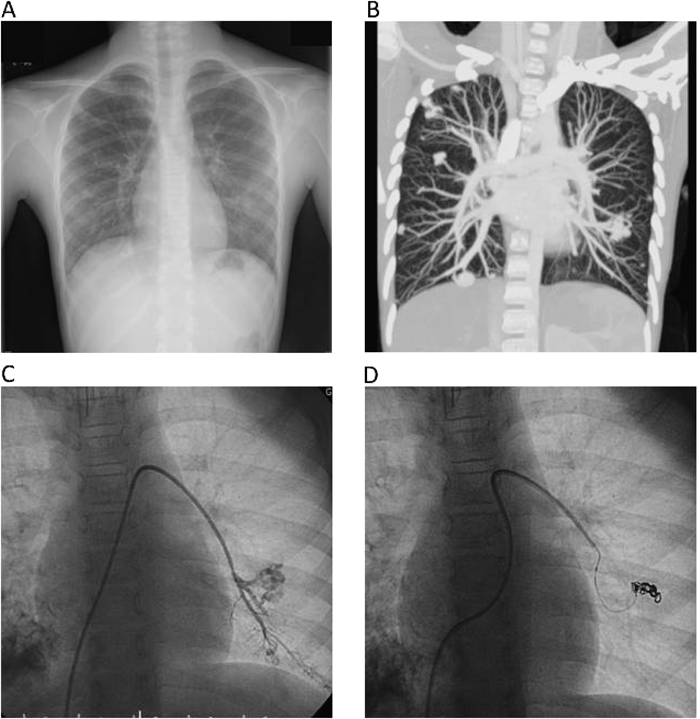

正常肺組織を犠牲にすることを前提としてコイル塞栓術を施行した両側肺全区域びまん性肺動静脈瘻の1例A Case of Diffuse Pulmonary Arteriovenous Malformationss Successfully Treated by Percutaneous Transcatheter Embolization with Sacrifice of Normal Pulmonary Arteries